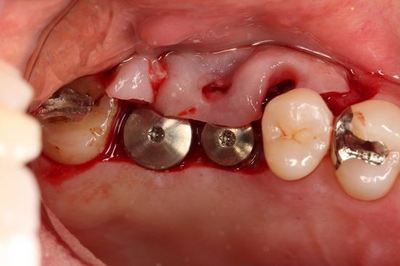

いよいよ本日のオペに臨みます。

左上臼歯部のミラー像です。

口腔内での適合を確認します。

スリーブの長さがありますので狭い口腔内でドリルを挿入するのは

熟練が必要です。